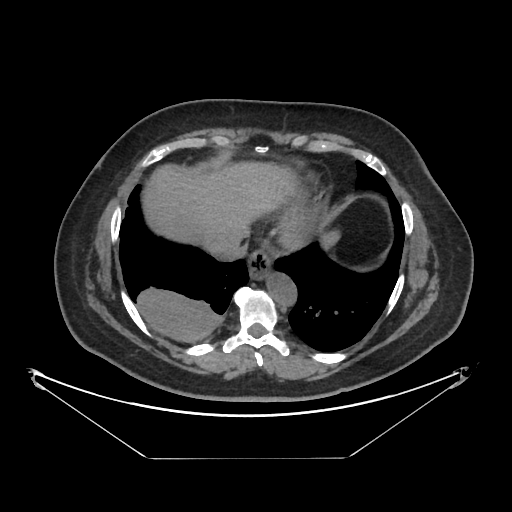

Original NATIVE CT scan (input)

Full window (WL 1023.5, WW 4095 β†’ Low βˆ’1024, High +3071)

Actual HU range: [-160.0, 240.0]

Lung window (WL -600, WW 1500 β†’ Low βˆ’1350, High +150)

Actual HU range: [-160.0, 150.0]

Mediastinum window (WL 40, WW 400 β†’ Low βˆ’160, High +240)